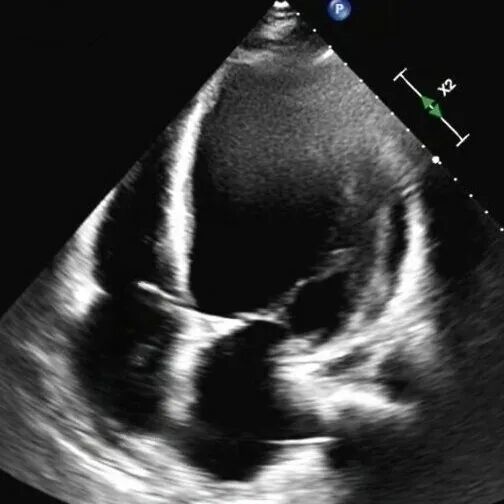

61岁的李先生(化名)三年前就偶尔出现胸闷乏力,一个月前,他因夜间无法平卧、呼吸极度困难,被紧急送往Beat365中国唯一官方网站第一附属医院(第一临床医学院)心脏重症监护室。通过系统检查,李先生左室舒张末期内径102mm(男性的正常值≤55mm),主动脉根部瘤样扩张63mm(正常≤35mm),左室射血分数仅21.83%(正常≥50%),心功能IV级(NYHA分级),主动脉瓣重度关闭不全,二尖瓣轻-中度关闭不全,最终确诊为终末期心衰,巨大心脏,主动脉根部瘤样扩张,随时发生主动脉夹层/主动脉破裂危及生命,此外主动脉瓣重度关闭不严,心功能极差,心脏随时可能“停摆”。

术前心脏超声